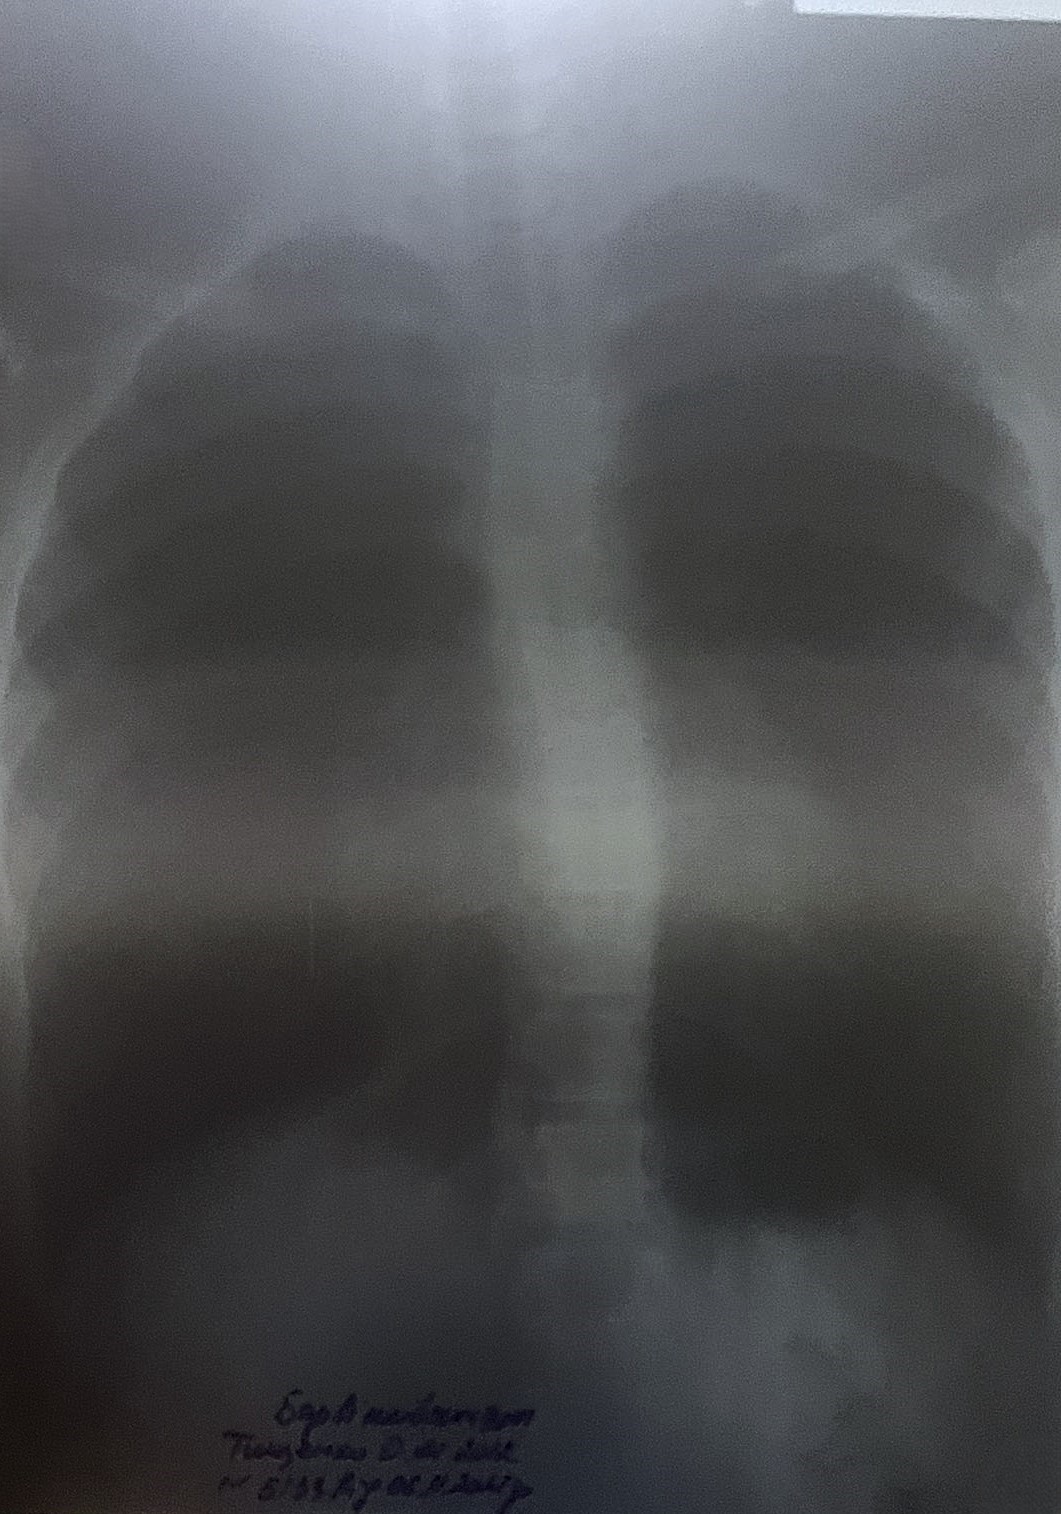

My son's name is Alexander. Until the age of 13, Sasha grew up as an ordinary, cheerful child - he talked with friends, helped with the housework, loved to play football. My son was happy with life and made plans for the future, dreaming of becoming a professional football player. But later I began to notice alarming changes. The child's mood suddenly disappeared, his appetite worsened, he stopped enjoying simple things. Soon physical symptoms appeared - shortness of breath began when walking, heart pain appeared, a funnel-shaped cavity in the chest cavity formed. We went to the hospital, underwent an examination, did a CT scan and visited an orthopedic doctor, who diagnosed our son with progressive chest deformity. At first, we were prescribed to wear a corset and do special exercises. We followed all the recommendations, hoping for improvement. But, upon re-examination, the doctor said that his son's condition requires surgical intervention using the Nass method - this is an operation with the installation of metal plates to correct the chest. Unfortunately, our family does not have the opportunity to independently collect the necessary amount for the operation and purchase of plates. I ask for help from all caring people. Please help my son breathe freely again, live without pain and feel like a full-fledged child. Angela Kolisnyk, Kharkiv region. Head of the Department of Orthopedics and Traumatology at the Mother and Child Center named after Rudnev Dmytro Petrenko (Dnipro): "Olexander has a progressive deformity of the chest. To avoid complications and disability, surgery is required to correct the curvature using minimally invasive correction according to the Nass method. This correction method uses a metal implant that raises the sternum and stabilizes it. This technique has several advantages: the surgical trauma and the associated risk of complications are less, moreover, the patient can count on a shorter period of temporary disability". The supplier of the metal structure-implant issued an invoice for UAH 56 800.